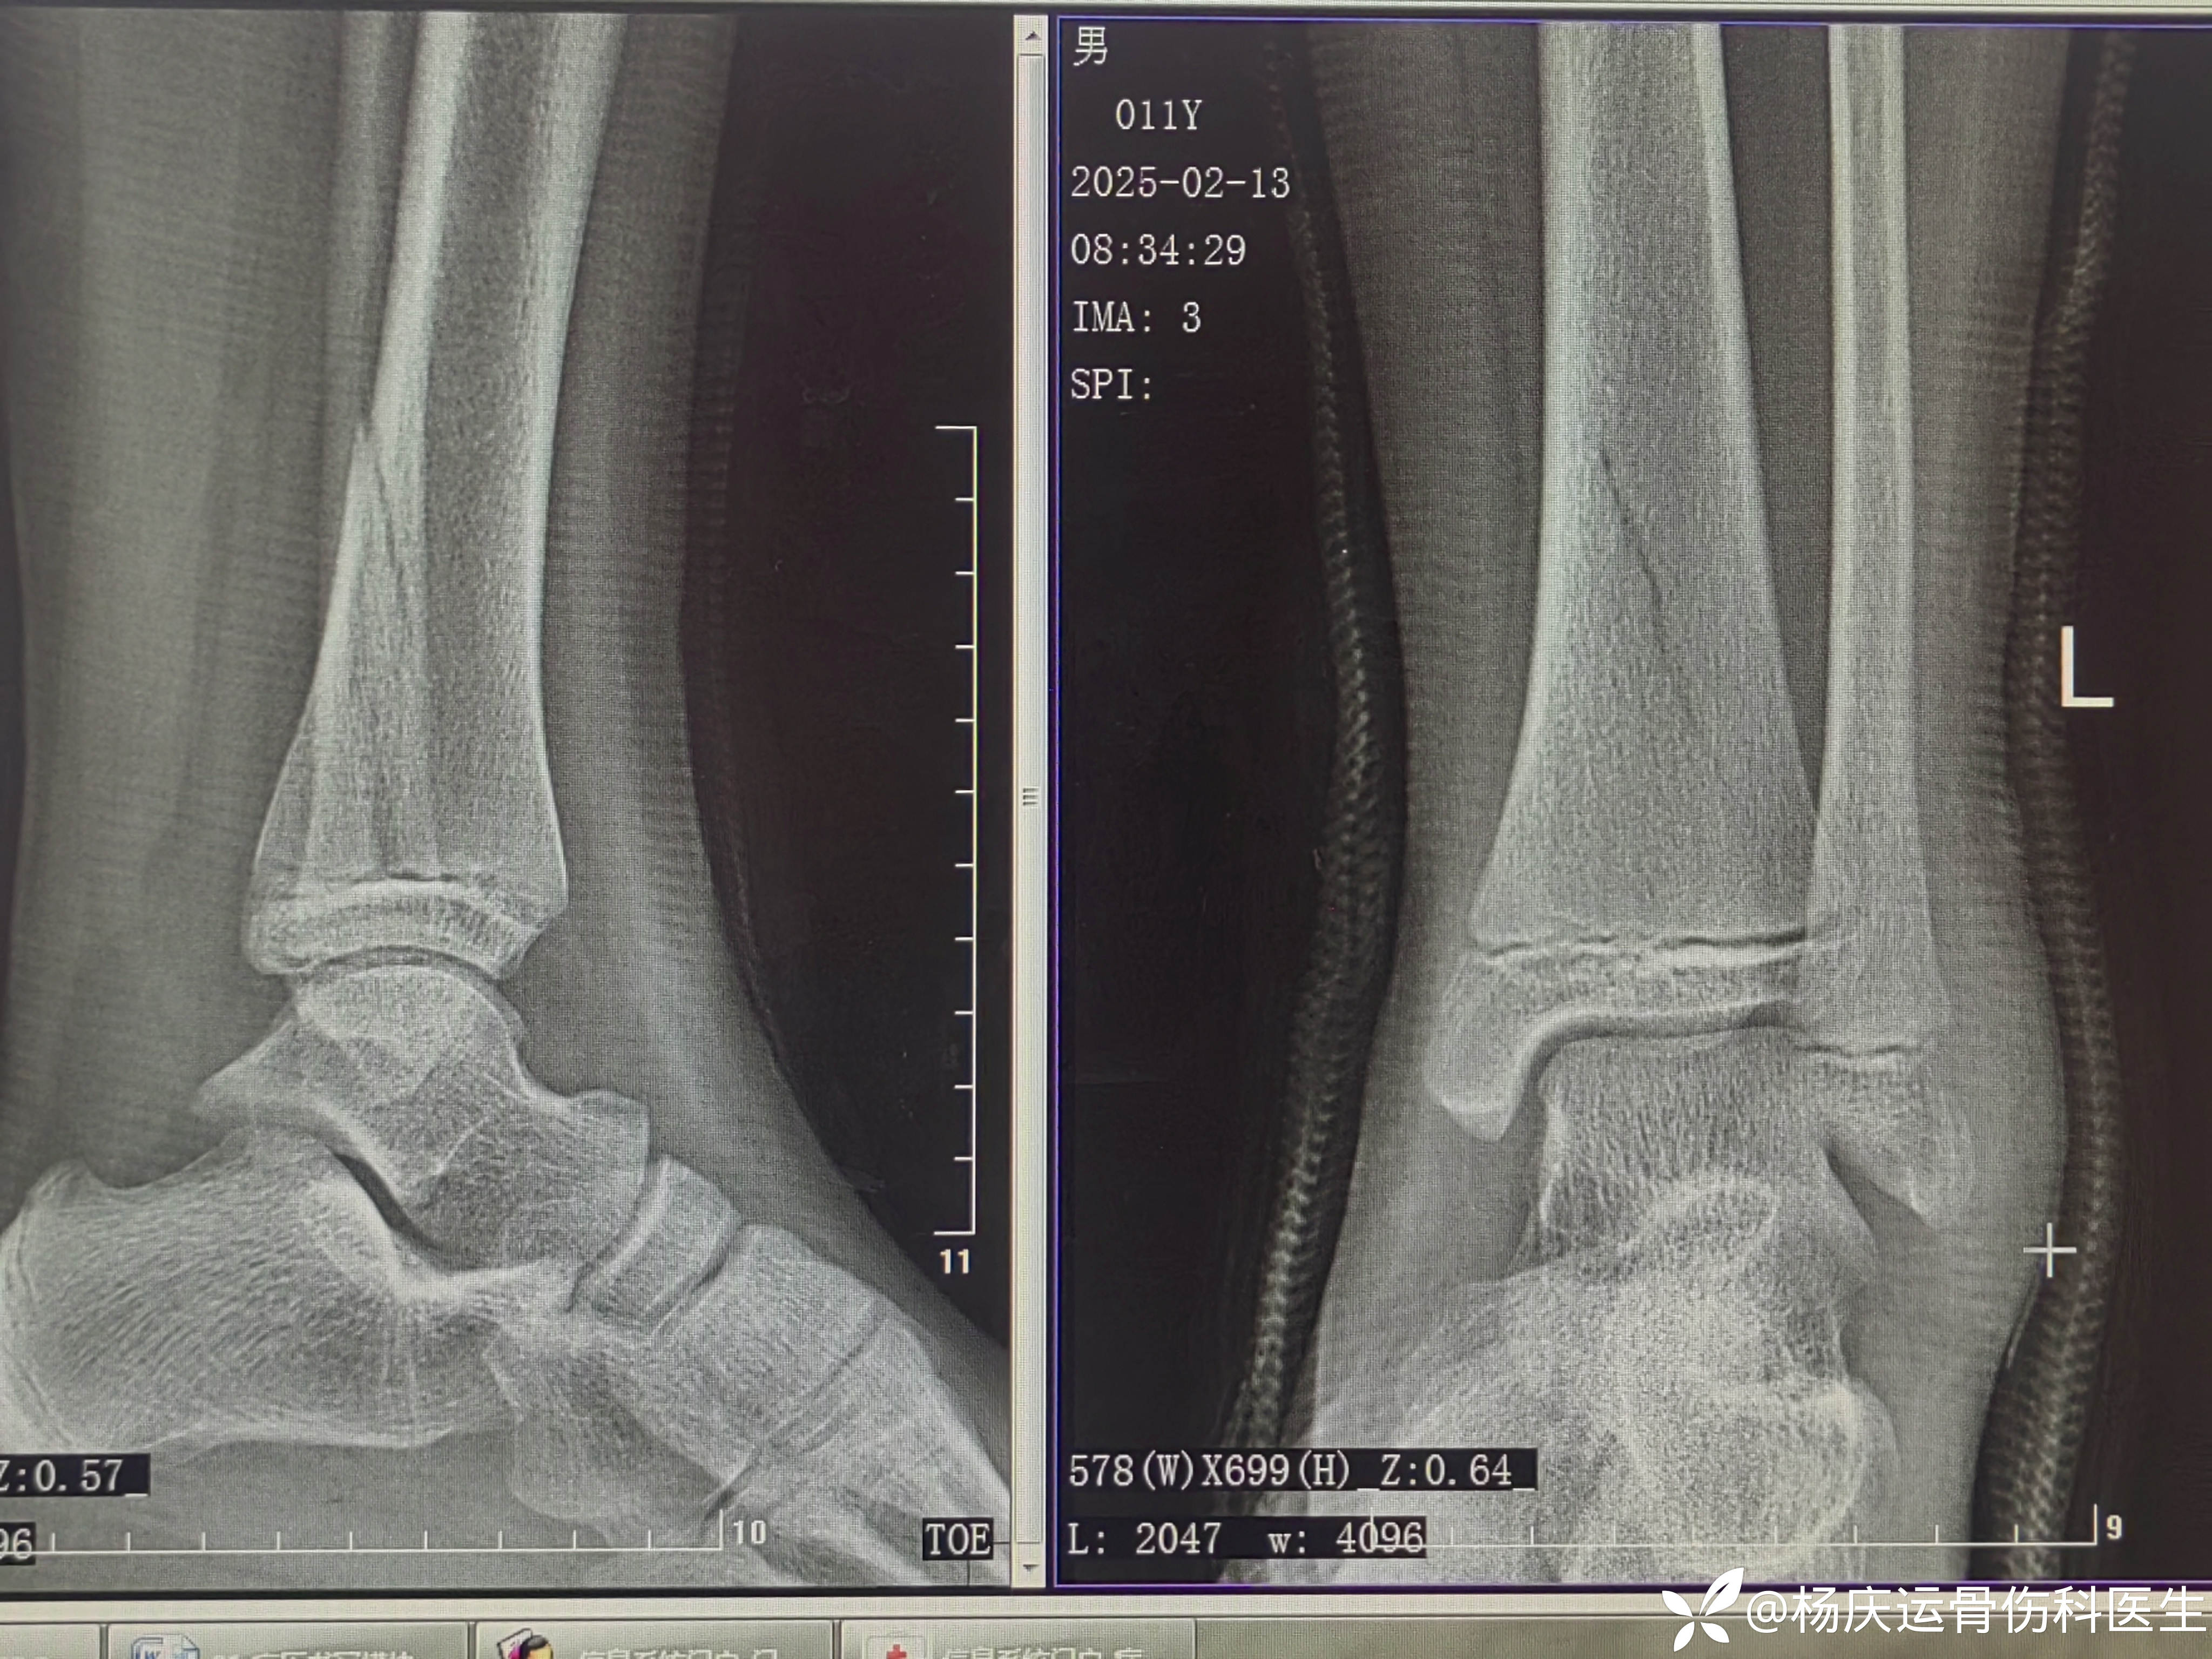

患者于,男,11岁,左踝外伤肿痛畸形活动受限2小时。2025-02-12来诊。

初步诊断:左胫骨远端骨骺骨折(S-H分型:II、III型)

首诊CT

骨折间隙3.0mm